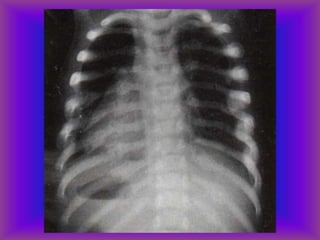

Lesiones Torácicas y

Abdominales

❖ Fracturas Costales

❖ Neumotórax – Hemotórax

Trauma Torácico

causante de

fracturas costales

Trauma Torácico: fracturas costales

Neumotórax

Hemotórax